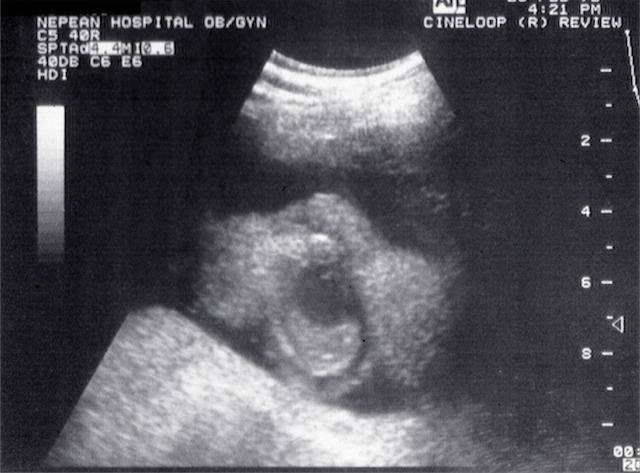

- Fetal anatomy

- Fetal kidney and liver 1969

| 1968 | Demonstration of fetal orbits, heart, bladder, kidneys and scrotum |

| 1970 | Introduction of grey scale ultrasound, improving dramatically the demonstration of normal and abnormal structures in the fetus, placenta and mother |